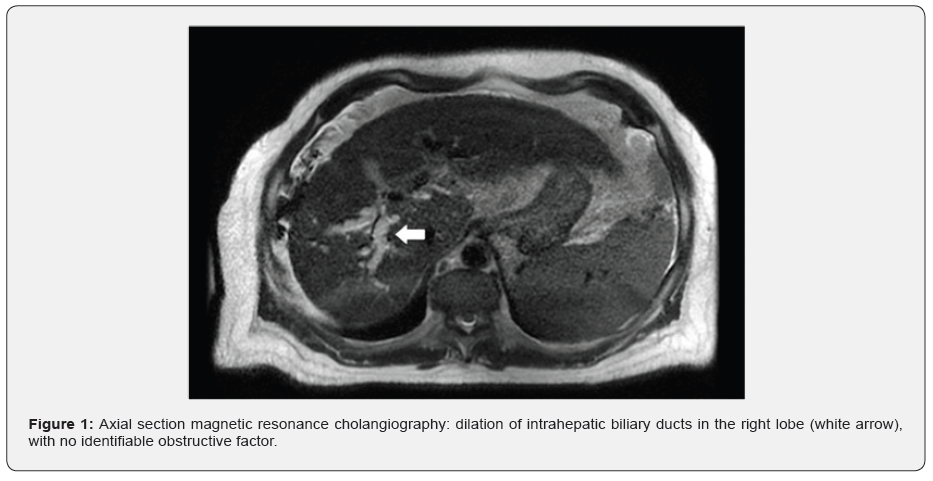

A 48-year-old man with metabolic-dysfunction associated fatty liver cirrhosis was first on the transplant waitlist. Upon hospital admission, he complained of jaundice over the past month. Laboratory: total bilirubin 31.6 mg/dL (normal range <1.2); direct bilirubin 25.7 mg/dL (<0.2); alkaline phosphatase 200 U/L (<104); international normalized ratio 1.64 (<1.25). Serum alpha-fetoprotein was normal and all cultures were negative. Both ultrasound, tomography and magnetic resonance cholangiography (Figure 1) showed a biliary dilation of the right hepatic lobe, with no evidence of an obstructive factor. He had a normal enhanced tomography for hepatocellular carcinoma (HCC) surveillance (because of obesity) two months before. With no signs of infection, a transplantation was performed.